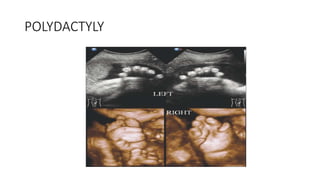

HANDS AND FEET

• Pre- or postaxial polydactyly (presence of more

than 5 fingers)

• Syndactyly :soft tissue or bony fusion

• Clinodactyly : Deviation of finger

• Any other deformities : hitchhiker’s thumb, rocker-

bottom feet, and clubbed feet or hands

POLYDACTYLY